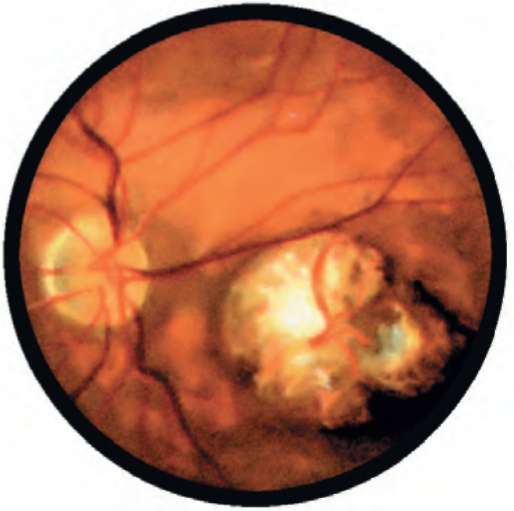

Рис. 26.1. Центральный токсоплазмозный хориоретинит

Рис. 26.2. Гранулематозный токсоплазмозный хориоретинит